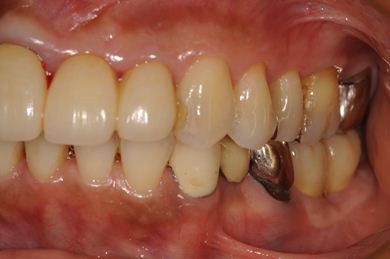

インプラントの症例写真 IMPLANT

インプラント治療+セラミック治療

| 主訴 | 上の前歯の左側の1本が下がって来て歯ぐきに時々炎症がある。右側下の歯ぐきに時々炎症及び鈍痛がある。 | ||||||||||||||||||||||||||||||||

| 治療内容 | インプラント2本、オールセラミック4本(ジルコニアフレーム、オールセラミック用の土台1本) | ||||||||||||||||||||||||||||||||